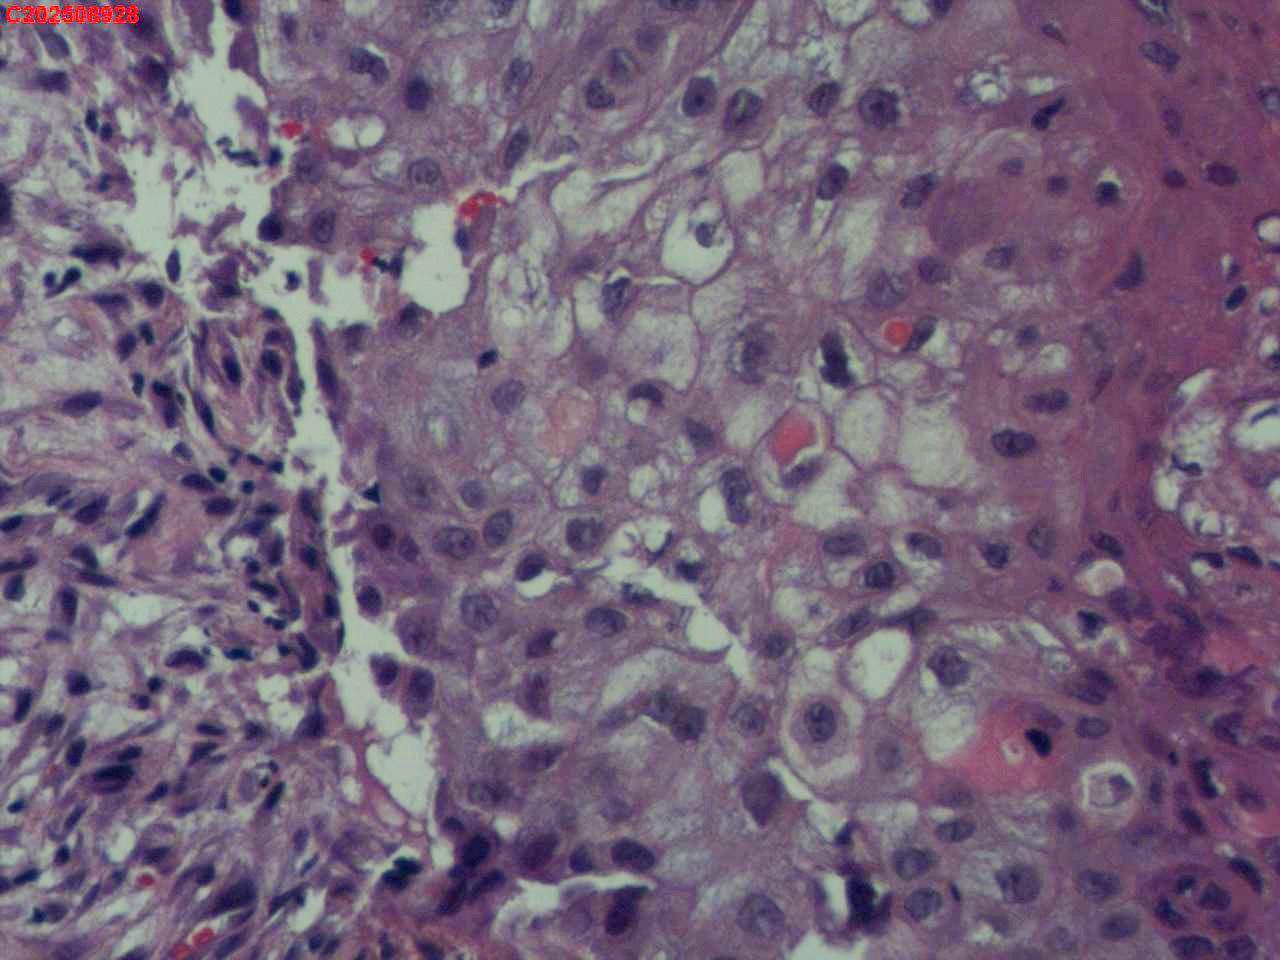

喉部右侧、声带下方咬检

男

56岁

喉Ca?

咳嗽

喉室内右侧声带下方新生物。

考虑鳞癌

鳞癌,有微浸润